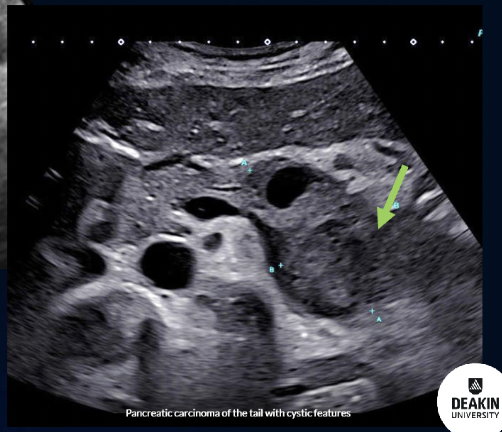

Path?

Tumour on the TAIL of Pancreas